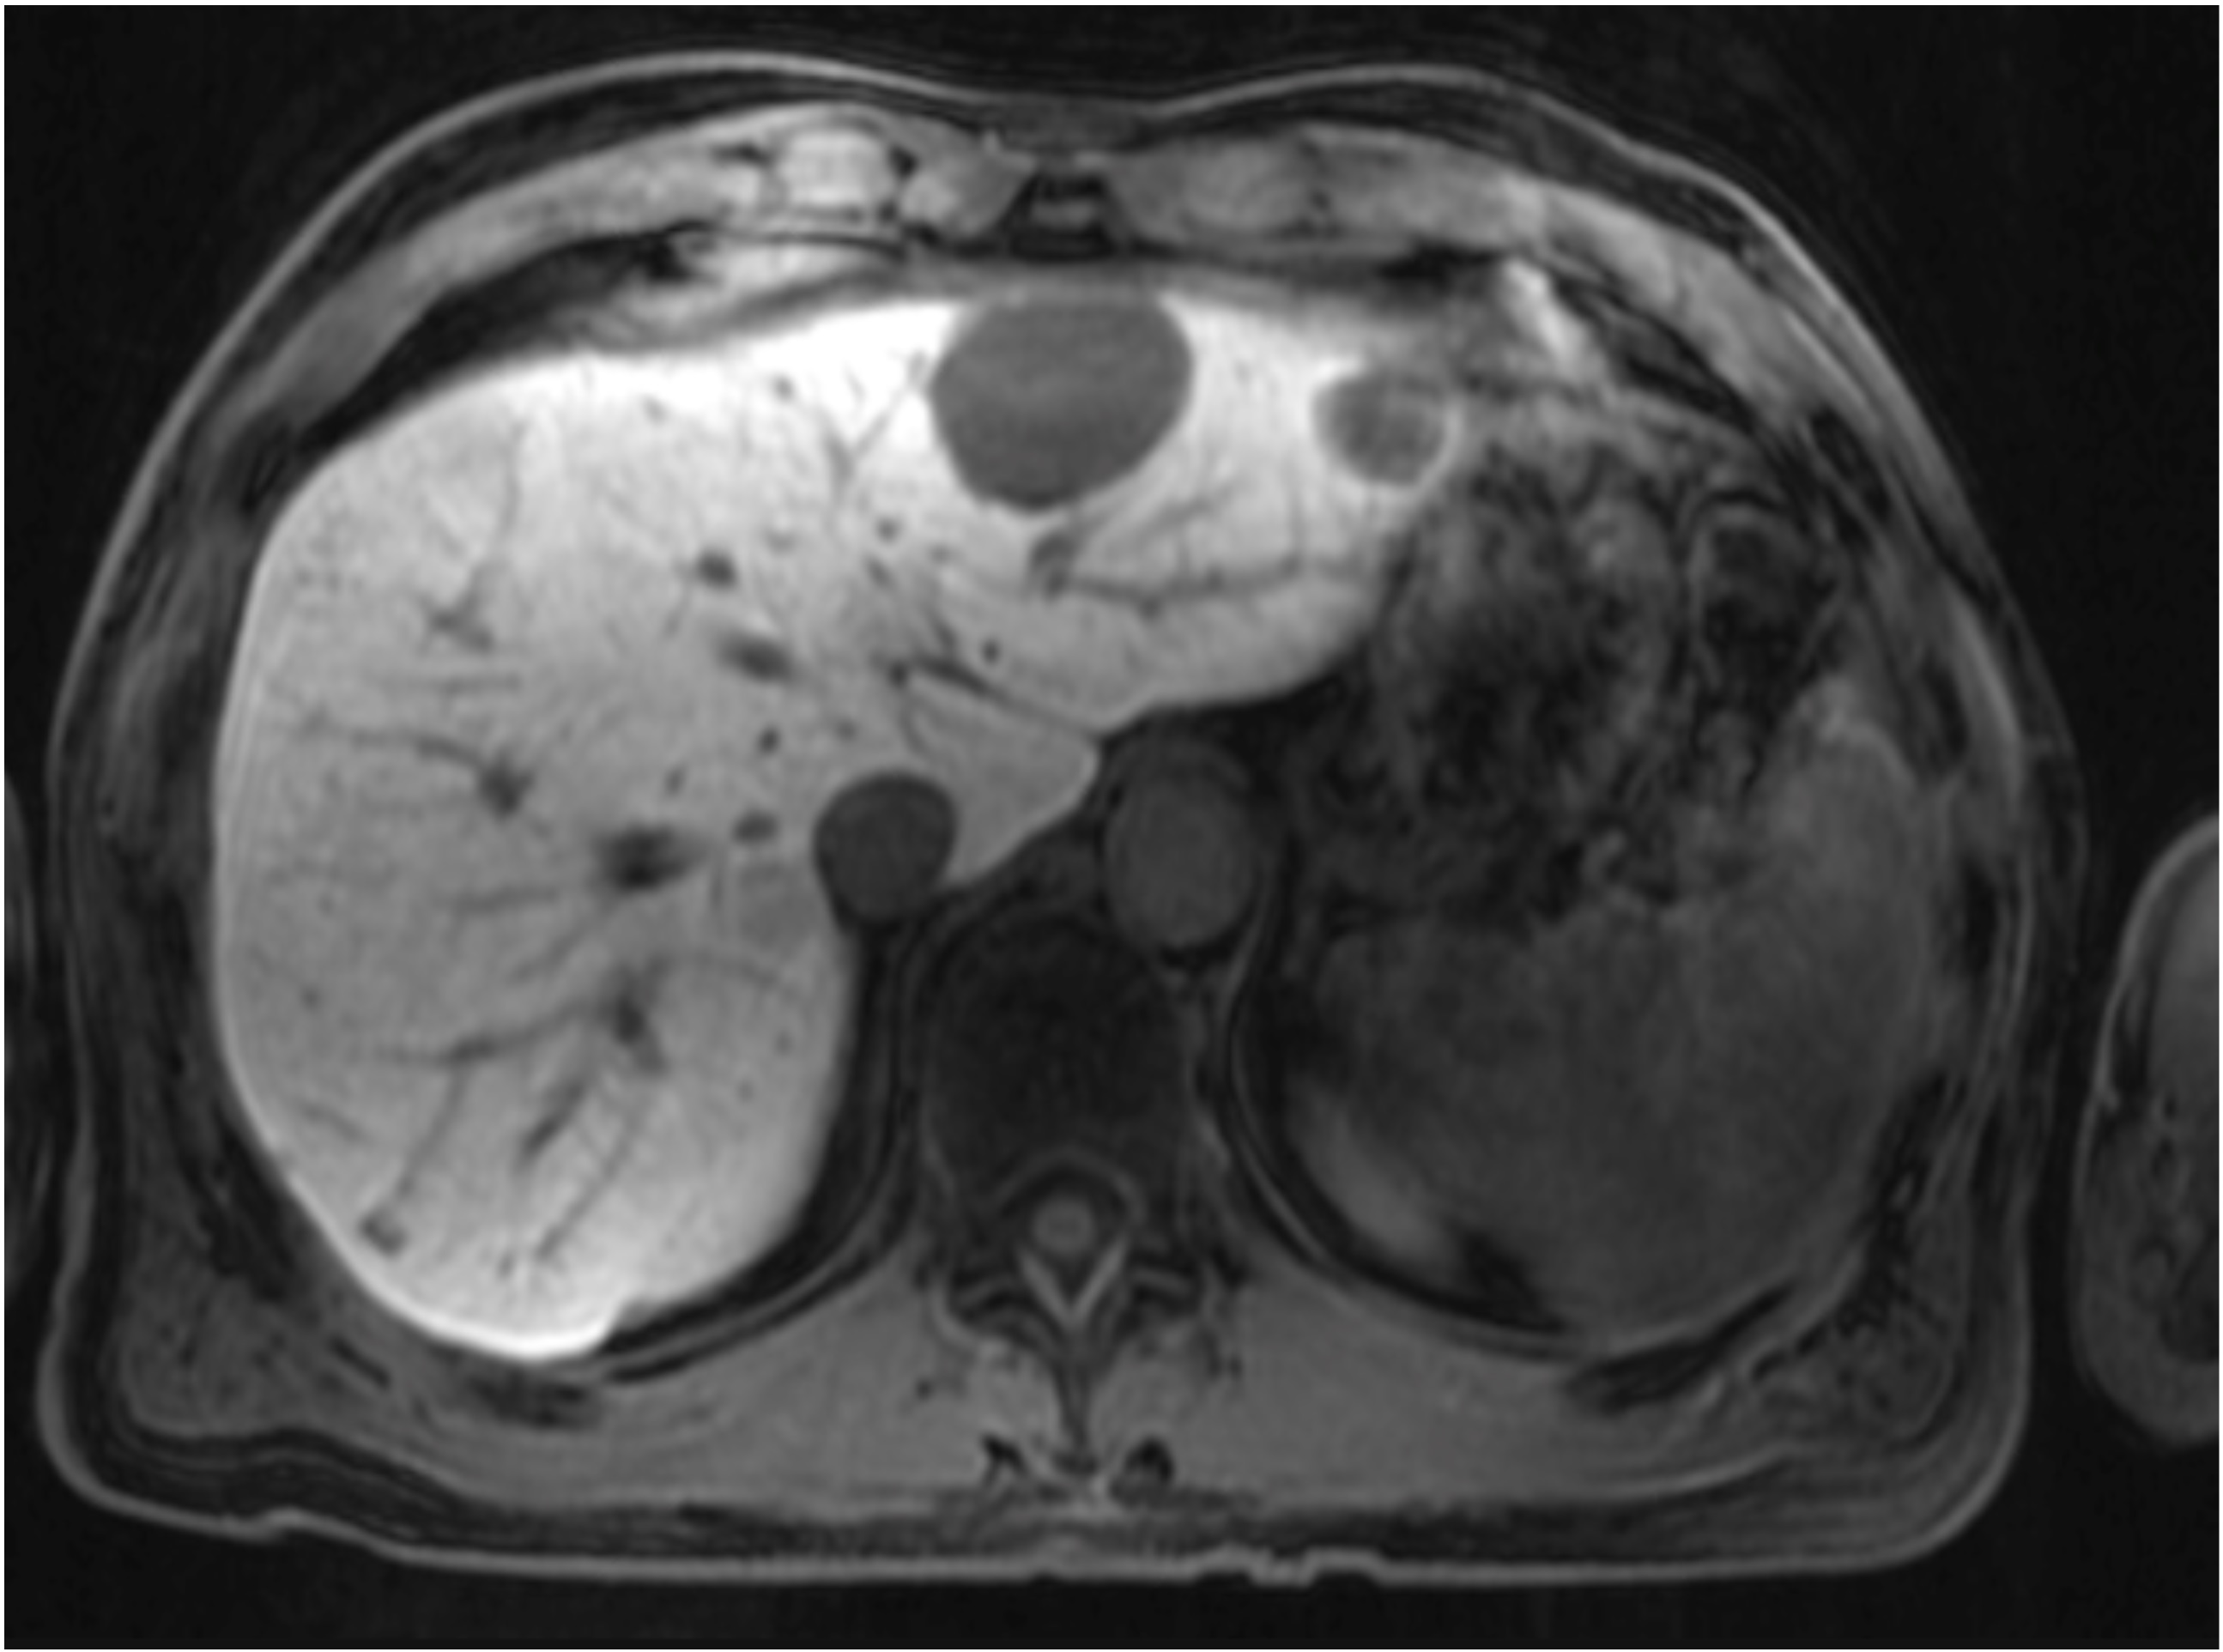

Gadobutrolenhanced MRI of the liver on a patient with hepatic What Is A Mri Of The Liver mri scans of the liver play a crucial role in diagnosing various liver conditions, including liver cancer, fatty. A group of blood tests called liver function tests can diagnose liver disease. imaging tests of the liver and gallbladder. It is a very useful tool for. a liver mri is capable of detecting many types of liver diseases,. What Is A Mri Of The Liver.

MRI of the liver. The right hepatic lesion is mildly hypointense on What Is A Mri Of The Liver By yedidya saiman, md, phd, lewis katz school of medicine, temple university. a liver scan describes a specialized imaging test that examines the liver to help identify certain conditions,. mri uses a type of tube scanner to provide a more detailed view of your organs than a ct scan. It is a very useful tool for. A group. What Is A Mri Of The Liver.

MRI of the liver. (a) T1 with fat saturation, (b) T2, (c) T1 + contrast What Is A Mri Of The Liver Liver mri takes from 10 to 30 minutes and does not. Other blood tests can be. imaging tests of the liver and gallbladder. mri uses a type of tube scanner to provide a more detailed view of your organs than a ct scan. A group of blood tests called liver function tests can diagnose liver disease. a. What Is A Mri Of The Liver.